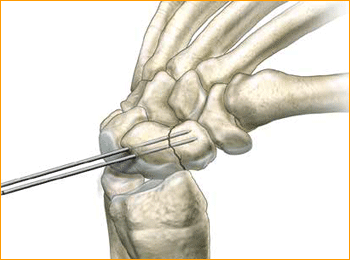

2. FRACTURE STABILIZATION

If the fracture is unstable it may be helpful to place a second parallel guide wire using the parallel wire guides.

3. DETERMINE SCREW LENGTH

Measure guide wire length using either the percutaneous screw sizer, or by placing a second wire at the entry point and subtracting the difference. The screw sizer cannot be used with the arthroscopic technique due to the limited access. Subtract 4 mm from the measured length to ensure that both ends of the screw are buried within the bone.

4. ADVANCE GUIDE WIRE

Advance the guide wire through the far cortex so that it lies in the subcutaneous tissues. This minimizes the risk of accidental withdrawal of the guide wire while drilling and facilitates wire removal if it should break.

Tip: For most adult males the screw should not be longer than 26 mm, and in females 22 mm.